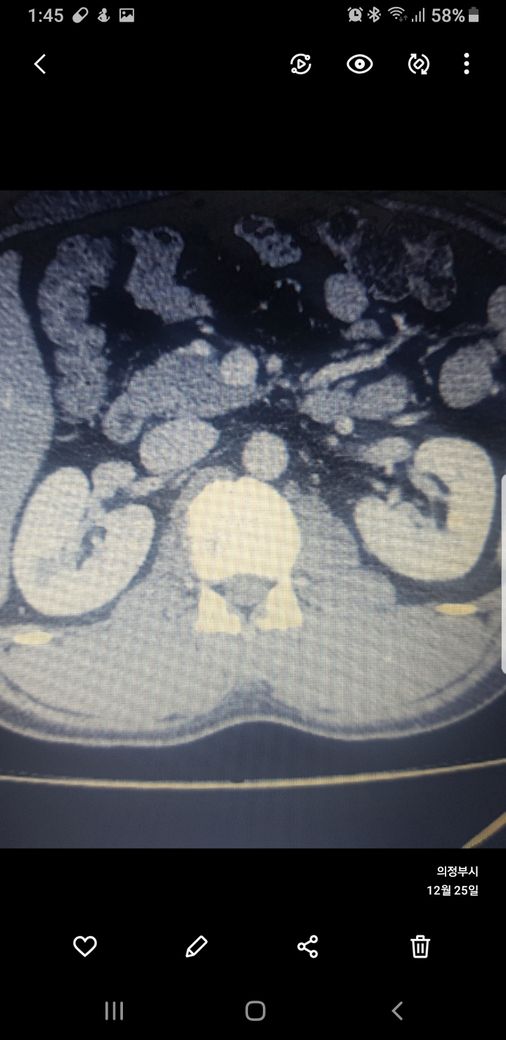

복부ct 작년 11월 , 올해 12월 촬영분입니다.

우측신장에 작년에는 1.7cm 물혹이 올해는 같은곳에 1.2cm 출혈성낭종이라는데

사진 1~4번째 는 작년